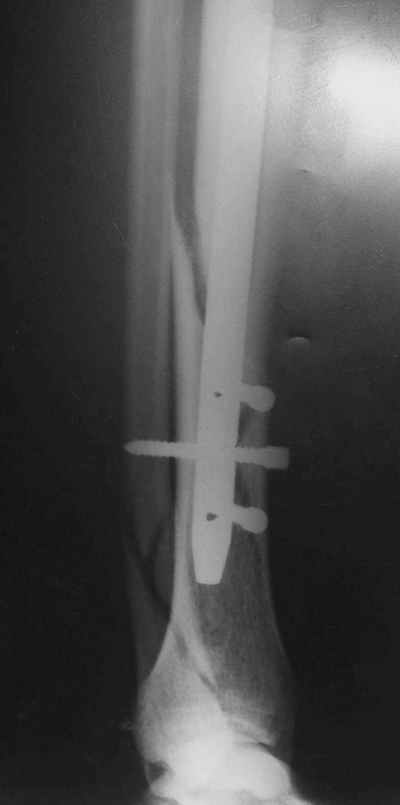

Потекли дистальные винты!

В дистальном отломке три винта( два медио-латеральных и один вентро-дорзальный).

Медио-латеральные вынты - мимо блокирующих отверстий фиксатора, вентро -

дорзальный винт - в отверстии.

Проблемы с верхним дистальным медио - латеральным винтом - он в линии перелома (

перелом косой).

Выполненный остосинтез нестабилен. Штифт надо заменить по "размеру" на солидный, дистльно три запирающих винта. Успехов!

Перелом спиральный, то есть низкоэнергетический, так что со сращением дело обстоит уже неплохо, лишь бы "костоеда" не развилась. Отломки выглядят уже стабилизированными костной мозолью, так что довводить винты, наверно, уже незачем. Разве что при клинической оценке подвижность еще есть - тогда можно для стабилизации наложить простейший аппарат, не опасаясь контакта его элементов с гвоздем, поскольку места в дистальном метафизе оставлено более чем достаточно.